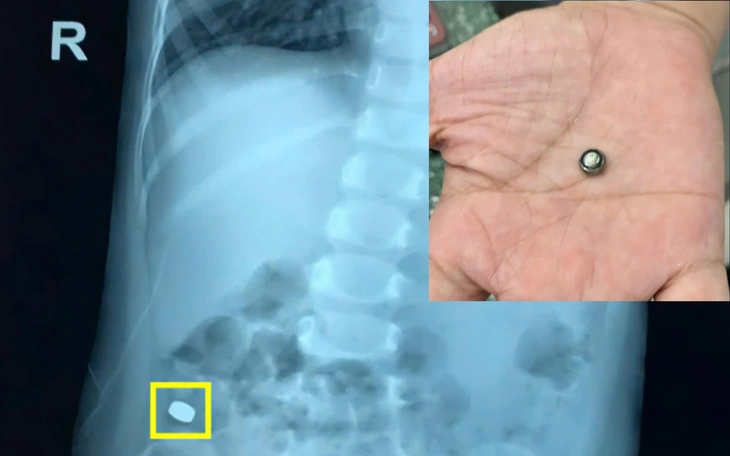

Ngay sau đó, bệnh nhi được thăm khám và chỉ định chụp X-quang để xác định. Kết quả bác sĩ phát hiện bệnh nhi có dị vật cản quang ở vùng cổ và cả dị vật cản quang trong ổ bụng…

Sau can thiệp nội soi lấy dị vật, bệnh nhi tỉnh táo và ổn định, hết đau vùng họng. Riêng dị vật ở vùng ổ bụng các bác sĩ kiểm tra, yêu cầu theo dõi sát và sau 4 ngày, bé trai đã đi vệ sinh ra 6 viên nam châm dính liền nhau.